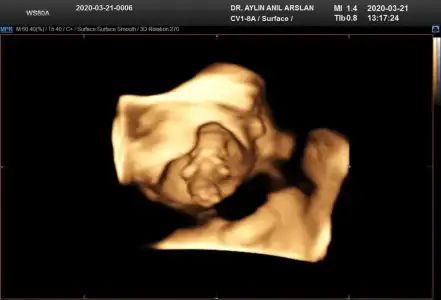

11+3 ama cok net değil gibi sanki yinede Bi tahmin isterim daha 5 hafta sonra öğrencez mecbur 😪

• IMG-20200321-WA0009.webp

IMG-20200321-WA0009.webp

17,6 KB · Görüntüleme: 34